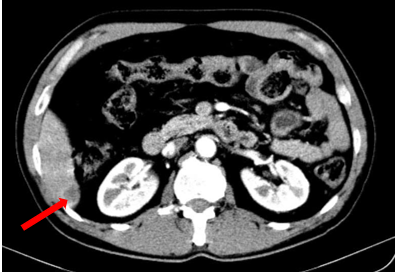

Bệnh nhân được chỉ định các xét nghiệm phương tiện cận lâm sàng khác. Trên phim chụp cắt lớp vi tính lồng ngực – ổ bụng của bệnh nhân phát hiện khối u phổi có kích thước ~ 32 x 30 mm ở thùy trên phổi trái và hình ảnh khối u gan ngấm thuốc viền – theo dõi thứ phát.

Hình 2. Hình ảnh khối u phổi phải trên phim chụp Cắt lớp vi tính ngày 19 tháng 03 năm 2025 (mũi tên).

Hình 3. Hình ảnh khối u gan (mũi tên)

Sau 3 chu kỳ điều trị, bệnh nhân được làm lại các xét nghiệm và chụp lại kiểm tra. Kết quả cho thấy kích thước các khối u đều giảm đáng kể, thẻ hiện sự đáp ứng tốt với liệu trình điều trị của bệnh nhân

Hình 4. Hình ảnh phim chụp cắt lớp vi tính ngực ngày 10 tháng 7 năm 2025 (mũi tên vàng) so với ngày 19 tháng 03 năm 2025 (mũi tên đỏ), kích thước khối u giảm đáng kể so với phim chụp cũ.

Hình 5. Hình ảnh phim chụp cắt lớp vi tính bụng ngày 10 tháng 7 năm 2025 (mũi tên trắng) so với ngày 19 tháng 03 năm 2025 (mũi tên đỏ) cho thấy hình ảnh khối u gan đã gần như biến mất hoàn toàn.